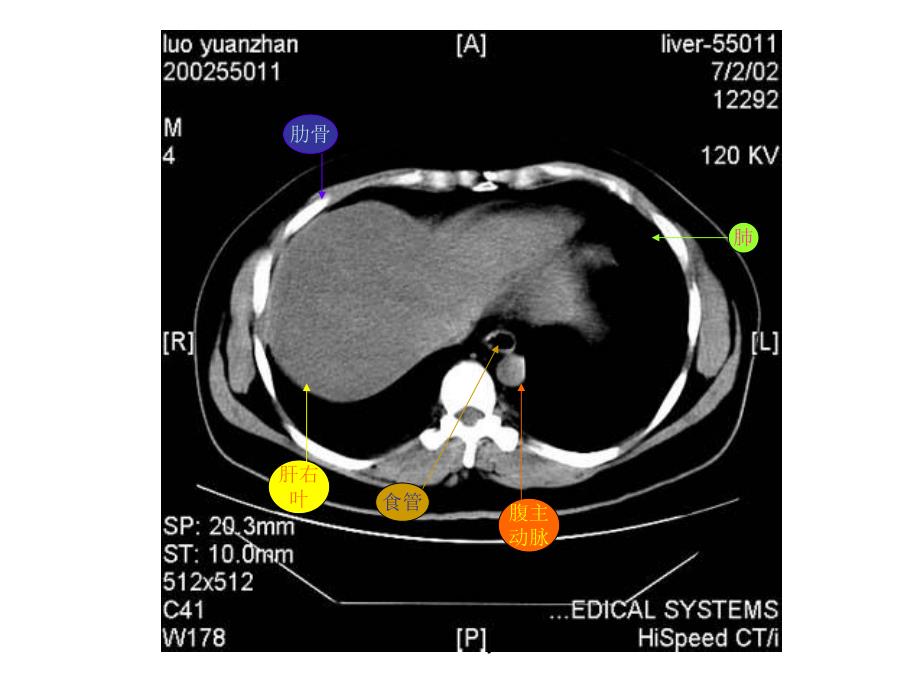

1、博益园 肝右叶横膈肺胸椎脊髓腹主动脉食管肋骨博益园 肋骨肝右叶腹主动脉食管肺博益园 肝左叶肝右叶腹主动脉胃脾肝尾叶博益园 肝右叶尾叶膈脚脾门静脉肝左叶胃博益园 肝右叶膈脚腹主动脉脾胆囊胃博益园 肝右叶下腔静脉胰腺脾胃腹主动脉博益园 肝右叶心脏腹主动脉下腔静脉脊髓食管肺博益园 肝左叶肝右叶腹主动脉下腔静脉胃脾脊髓博益园 肝左叶及肝左动脉肝右叶及肝右动脉腹主动脉下腔静脉胃脾肝尾叶博益园 肝右叶下腔静脉腹主动脉胃脾膈脚博益园 肝静脉下腔静脉腹主动脉食道肝右叶博益园 下腔静脉肝右叶肝静脉肝左叶腹主动脉胃脾肝尾叶博益园 肝右叶下腔静脉腹主动脉门静脉主干肝左叶胃脾博益园 肝右叶下腔静脉门静脉腹主动脉膈脚脾